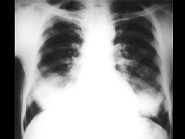

单项选择题女,34岁, 新月体肾炎患者,最近咳嗽咯血, 第一次行胸片检查考虑为双下肺感染,抗感染治疗后无明显好转, 症状加重,4天后复查并行CT检查如图, 应考虑为 ( )